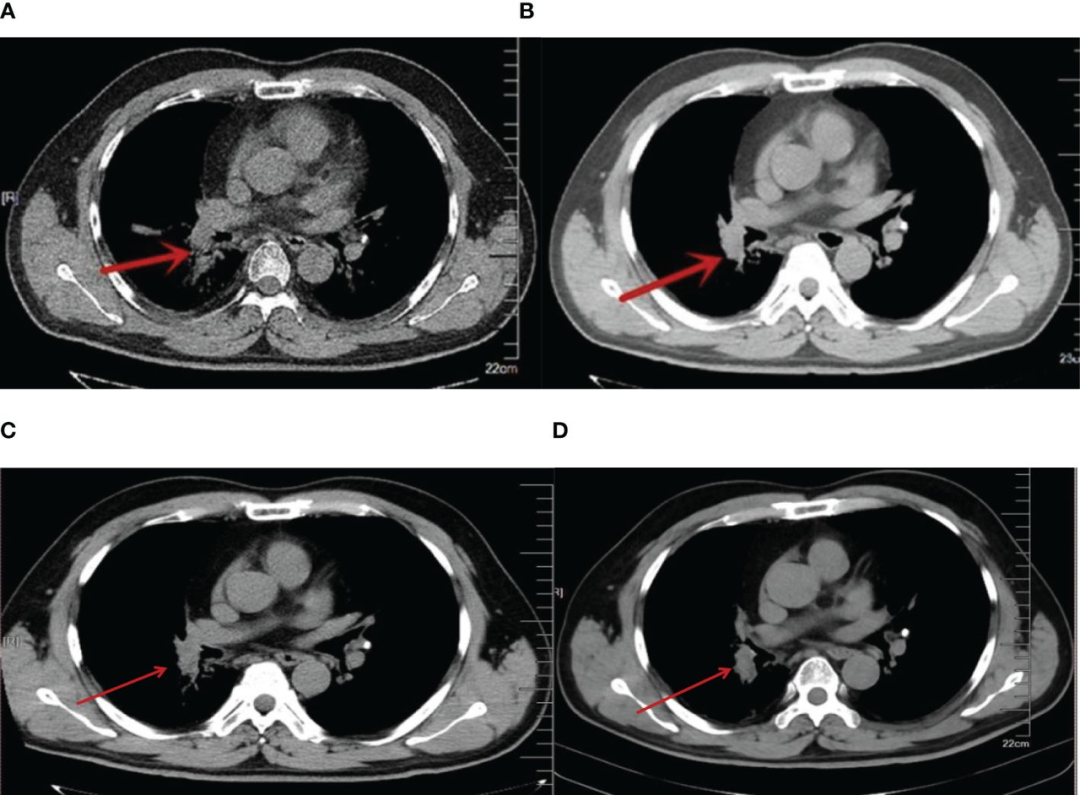

图片

患者的肺部CT扫描:A. 2013年化疗后;B. 2013年细胞疗法与化疗的联合治疗后;C.2016年;D.2023年。

经过前4个月的联合治疗,影像学复查结果显示,患者右肺的原发肿瘤明显缩小(如下图所示)。在随后的治疗和随访中,患者的病灶逐步趋于稳定。

在经历了两年的细胞疗法与化疗相结合的治疗后,患者的病灶控制效果理想,且未出现其他明显的不良反应。从2011年确诊至今,患者已存活长达13年,远远超出广泛期小细胞肺癌的预期生存期。